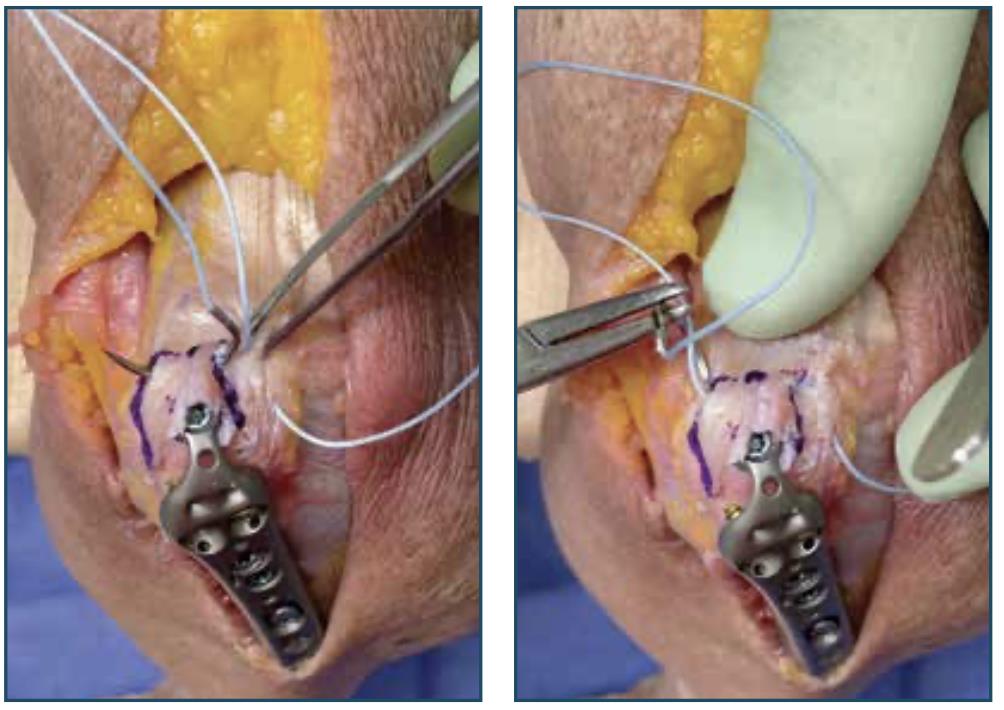

• Continue Passing Suture

• continue passing the suture deep along the olecranon surface and the distal outline, incorporating Sharpey’s fibers

• continue the deep-running stitch medially

• Pass Suture Through Plate

• pass the suture through the medial suture hole of the plate, then pass the suture through the lateral suture hole of the plate

• Tie Sliding Knot

• tighten the suture to remove all slack

• pull suture limbs to confirm the suture slides within the tissue

• tie and tension a sliding knot on the lateral side

• Secure Construct

• secure the construct with six additional surgeon knots

• to avoid irritation of the soft tissue, ensure the knot stack is lateralized as much as possible